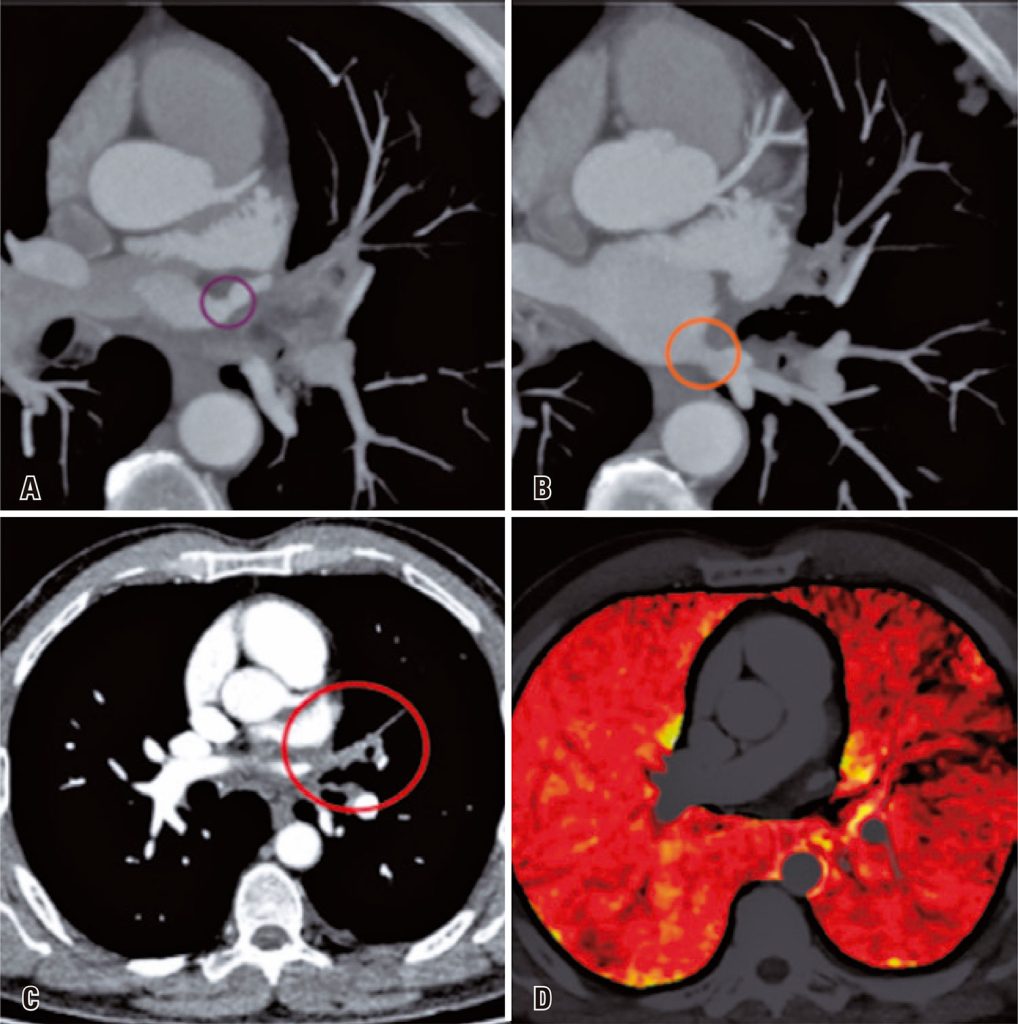

A 55-year-old male patient presented to the emergency department with ventilatory-dependent chest pain, 5 months after undergoing radiofrequency ablation for atrial fibrillation. Upon initial assessment, the patient exhibited an elevated D-dimer level of 1122ng/mL. Consequently, a computed tomography pulmonary angiogram (CTPA) was requested to investigate because of the possibility of a pulmonary thromboembolism. The CTPA ( ) revealed a focal reduction in the caliber of both the left upper and lower pulmonary veins ostia. Additionally, occlusion of the pulmonary venous branches upstream of the stenotic point was observed. The corresponding segmental pulmonary hypoperfusion within the territory drained by the stenosed veins was clearly illustrated in the iodine map images.